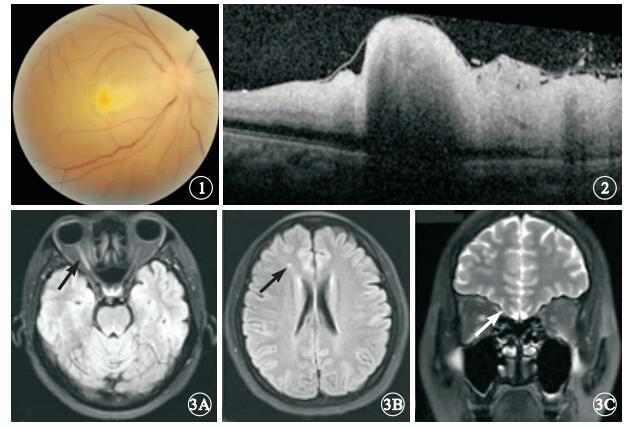

患者女,37歲。行隆鼻手術中突然右眼失明28 h于2013年9月4日來我院就診。患者1 d前在美容院行隆鼻手術,右側鼻根部位注射膠原蛋白0.5 ml,注射醫生在鼻根部注射部位給予按摩后患者隨即出現心悸、頭暈、惡心等不適。醫生判斷為過敏反應給予地塞米松10 mg肌肉注射,患者閉目休息。2 h后患者睜眼發現右眼視物不見,眼球周圍脹痛。當地醫院檢查,右眼視力無光感,眼底視網膜蒼白。診斷視網膜中央動脈阻塞(CRAO),給予硝酸甘油擴張血管等治療。為進一步診治來我院就診。眼科檢查:右眼視力無光感,左眼視力1.2。瞳孔直徑右眼5 mm,左眼3 mm。左眼直接對光反射正常,間接對光反射消失;右眼直、間接對光反射均消失。眼壓右眼8 mmHg(1 mmHg=0.133 kPa), 左眼12 mmHg。右眼上瞼下垂,遮蓋瞳孔上緣1/3,眼球各方向活動均受限;結膜無充血,角膜透明,房水混濁(+)。眼底檢查,視網膜彌漫性水腫,顏色蒼白;黃斑區灰白色隆起,未見櫻桃紅,視盤水腫(圖 1)。左眼眼前節、眼底檢查正常。頻域光相干斷層掃描(SD-OCT)檢查,右眼內層視網膜彌漫性水腫、高度隆起(圖 2)。眼部彩色多普勒檢查,右眼視網膜中央動脈、睫狀后動脈及眼動脈血流均未探及,球后僅探及低速反向眼上靜脈血流信號。眼眶MRI檢查,軸位T2加權見右側視神經全程強信號,后極部視網膜、右眼眶內眼外肌部分強信號;右側額葉點狀缺血灶,彌散加權(DWI)右視神經急性期缺血(圖 3)。因患者對熒光素鈉過敏,未行熒光素眼底血管造影檢查。全身檢查:血壓130/70 mmHg血常規、血糖、血脂和肝腎功能等實驗室檢查未見異常。診斷:右眼醫源性急性眼動脈栓塞。治療:靜脈給予甲潑尼龍琥珀酸鈉240 mg,連續3 d,同時輔以神經保護劑。1個月后隨訪,患者右眼視力無光感;眼前節未見異常;眼底黃斑區水腫消退,視盤下方和鼻側視網膜分支血管閉塞,視盤周圍視網膜前機化膜形成。上瞼高度及眼球運動基本恢復正常。眼壓正常。

圖1

右眼彩色眼底像。視網膜彌漫性水腫,顏色蒼白,黃斑區未見典型櫻桃紅,視盤水腫??圖 2??右眼SD-OCT像。內層視網膜明顯水腫,黃斑部高度隆起??圖 3??頭顱MRI像。3A.軸位T2 Flair加權,右側視神經全程強信號(黑箭);3B.右側額葉點狀缺血灶(黑箭);3C.Stair序列,右側視神經信號異常(白箭)

圖1

右眼彩色眼底像。視網膜彌漫性水腫,顏色蒼白,黃斑區未見典型櫻桃紅,視盤水腫??圖 2??右眼SD-OCT像。內層視網膜明顯水腫,黃斑部高度隆起??圖 3??頭顱MRI像。3A.軸位T2 Flair加權,右側視神經全程強信號(黑箭);3B.右側額葉點狀缺血灶(黑箭);3C.Stair序列,右側視神經信號異常(白箭)

患者女,37歲。行隆鼻手術中突然右眼失明28 h于2013年9月4日來我院就診。患者1 d前在美容院行隆鼻手術,右側鼻根部位注射膠原蛋白0.5 ml,注射醫生在鼻根部注射部位給予按摩后患者隨即出現心悸、頭暈、惡心等不適。醫生判斷為過敏反應給予地塞米松10 mg肌肉注射,患者閉目休息。2 h后患者睜眼發現右眼視物不見,眼球周圍脹痛。當地醫院檢查,右眼視力無光感,眼底視網膜蒼白。診斷視網膜中央動脈阻塞(CRAO),給予硝酸甘油擴張血管等治療。為進一步診治來我院就診。眼科檢查:右眼視力無光感,左眼視力1.2。瞳孔直徑右眼5 mm,左眼3 mm。左眼直接對光反射正常,間接對光反射消失;右眼直、間接對光反射均消失。眼壓右眼8 mmHg(1 mmHg=0.133 kPa), 左眼12 mmHg。右眼上瞼下垂,遮蓋瞳孔上緣1/3,眼球各方向活動均受限;結膜無充血,角膜透明,房水混濁(+)。眼底檢查,視網膜彌漫性水腫,顏色蒼白;黃斑區灰白色隆起,未見櫻桃紅,視盤水腫(圖 1)。左眼眼前節、眼底檢查正常。頻域光相干斷層掃描(SD-OCT)檢查,右眼內層視網膜彌漫性水腫、高度隆起(圖 2)。眼部彩色多普勒檢查,右眼視網膜中央動脈、睫狀后動脈及眼動脈血流均未探及,球后僅探及低速反向眼上靜脈血流信號。眼眶MRI檢查,軸位T2加權見右側視神經全程強信號,后極部視網膜、右眼眶內眼外肌部分強信號;右側額葉點狀缺血灶,彌散加權(DWI)右視神經急性期缺血(圖 3)。因患者對熒光素鈉過敏,未行熒光素眼底血管造影檢查。全身檢查:血壓130/70 mmHg血常規、血糖、血脂和肝腎功能等實驗室檢查未見異常。診斷:右眼醫源性急性眼動脈栓塞。治療:靜脈給予甲潑尼龍琥珀酸鈉240 mg,連續3 d,同時輔以神經保護劑。1個月后隨訪,患者右眼視力無光感;眼前節未見異常;眼底黃斑區水腫消退,視盤下方和鼻側視網膜分支血管閉塞,視盤周圍視網膜前機化膜形成。上瞼高度及眼球運動基本恢復正常。眼壓正常。

圖1

右眼彩色眼底像。視網膜彌漫性水腫,顏色蒼白,黃斑區未見典型櫻桃紅,視盤水腫??圖 2??右眼SD-OCT像。內層視網膜明顯水腫,黃斑部高度隆起??圖 3??頭顱MRI像。3A.軸位T2 Flair加權,右側視神經全程強信號(黑箭);3B.右側額葉點狀缺血灶(黑箭);3C.Stair序列,右側視神經信號異常(白箭)

圖1

右眼彩色眼底像。視網膜彌漫性水腫,顏色蒼白,黃斑區未見典型櫻桃紅,視盤水腫??圖 2??右眼SD-OCT像。內層視網膜明顯水腫,黃斑部高度隆起??圖 3??頭顱MRI像。3A.軸位T2 Flair加權,右側視神經全程強信號(黑箭);3B.右側額葉點狀缺血灶(黑箭);3C.Stair序列,右側視神經信號異常(白箭)